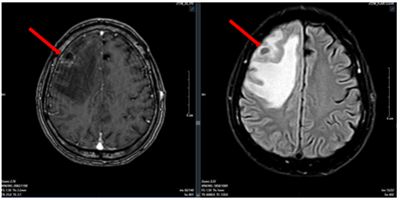

Ca lâm sàng: Điều trị đích bệnh nhân ung thư phổi không tế bào nhỏ giai đoạn muộn di căn nhiều cơ quan, tại Trung tâm Y học hạt nhân và Ung bướu – Bệnh viện Bạch Mai

Ung thư phổi là nguyên nhân hàng đầu gây tử vong do ung thư trên toàn thế giới. Trong đó, ung thư phổi không tế bào nhỏ (NSCLC) là thể thường gặp nhất, chiếm khoảng 85% các trường hợp [1]. Phần lớn bệnh nhân được chẩn đoán ở giai đoạn tiến...